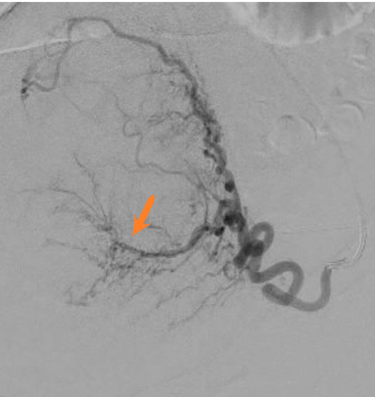

Image d'artériographie d'une procédure d'embolisation utérine du côté droit et gauche chez une même patiente.

Les formations tubulées noires correspondants aux artères et vaisseaux sanguins telles que visualisées par le radiologue interventionnel lors de l'injection de produit de contraste.

On individualise successivement le cathéter permettant l'injection du produit (flèche noire), l'artère utérine (flèche rouge) avec visualisation d'un des fibromes utérines à traiter chez cette patiente (flèche orange) sous forme d'un réseau artériel en arc de cercle.